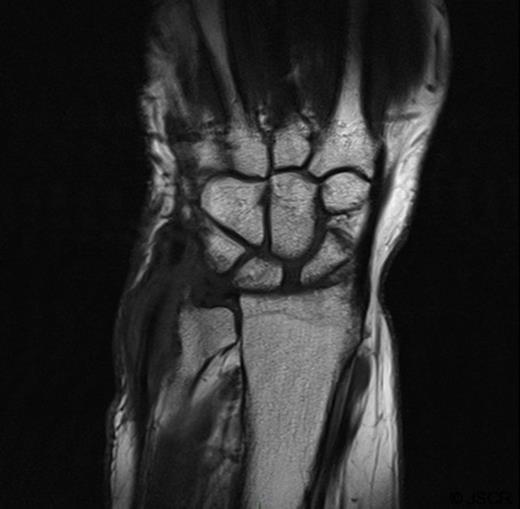

She was subsequently referred to the hand clinic. X ray this time showed destruction of the ulnar styloid consistent with a bony infection (Figure 2). MRI showed destruction localised around the ulnar head with oedematous changes extending up the shaft of the ulna (Figure 3).

AP Xray of the wrist showing destruction of the ulnar styloid consistent with a bony infection. Soft tissue swelling can also be noted over the dorsum of the wrist